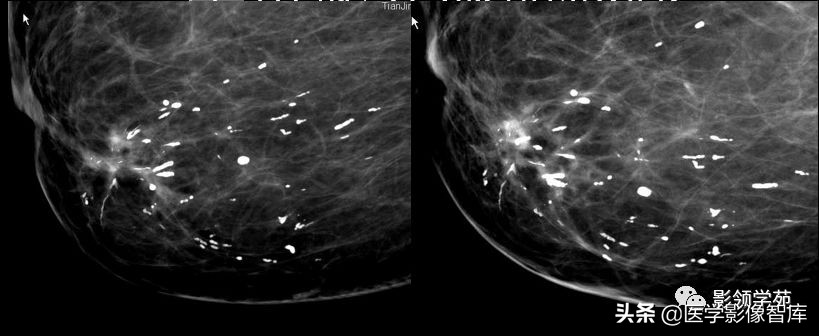

浸润性导管癌,多形性钙化、线虫状、分支杆状钙化。

女,50岁,多簇状细小多形性钙化,右乳外上浸润性导管癌。

不规则肿物伴多形性钙化,浸润性导管癌